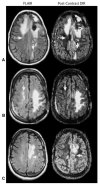

Fluid attenuated inversion recovery (FLAIR) MRI sequences have become an indispensible tool for defining the malignant boundary in patients with brain tumors by nulling the signal contribution from cerebrospinal fluid allowing both regions of edema and regions of non-enhancing, infiltrating tumor to become hyperintense on resulting images. In the current study we examined the utility of a three-dimensional double inversion recovery (DIR) sequence that additionally nulls the MR signal associated with white matter, implemented either pre-contrast or post-contrast, in order to determine whether this sequence allows for better differentiation between tumor and normal brain tissue. T1- and T2-weighted, FLAIR, dynamic susceptibility contrast (DSC)-MRI estimates of cerebral blood volume (rCBV), contrast-enhanced T1-weighted images (T1+C), and DIR data (pre- or post-contrast) were acquired in 22 patients with glioblastoma. Contrast-to-noise (CNR) and tumor volumes were compared between DIR and FLAIR sequences. Line profiles across regions of tumor were generated to evaluate similarities between image contrasts. Additionally, voxel-wise associations between DIR and other sequences were examined. Results suggested post-contrast DIR images were hyperintense (bright) in regions spatially similar those having FLAIR hyperintensity and hypointense (dark) in regions with contrast-enhancement or elevated rCBV due to the high sensitivity of 3D turbo spin echo sequences to susceptibility differences between different tissues. DIR tumor volumes were statistically smaller than tumor volumes as defined by FLAIR (Paired t test, P = 0.0084), averaging a difference of approximately 14 mL or 24 %. DIR images had approximately 1.5× higher lesion CNR compared with FLAIR images (Paired t test, P = 0.0048). Line profiles across tumor regions and scatter plots of voxel-wise coherence between different contrasts confirmed a positive correlation between DIR and FLAIR signal intensity and a negative correlation between DIR and both post-contrast T1-weighted image signal intensity and rCBV. Additional discrepancies between FLAIR and DIR abnormal regions were also observed, together suggesting DIR may provide additional information beyond that of FLAIR.